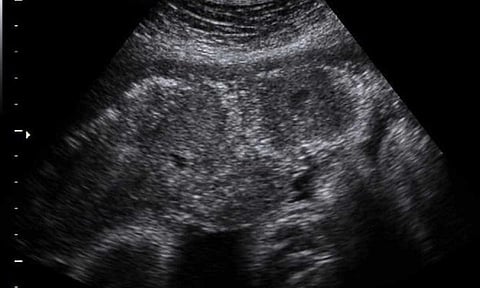

أكدت استشارية طب النساء والولادة الدكتورة مها النمر، أن تكلس المشيمة لا يشكل أي خطورة على الجنين، ولا يحتاج إلى إجراء الطلق الصناعي والتوليد.

وأوضحت النمر، في تغريدة عبر حسابها الرسمي على تويتر، أنه لا يهم درجات تكلس المشيمة، إذا كان نمو الجنين سليما، وكذلك السوائل جيدة، وتدفق الدم في الحبل السري سليم.

وأشارت إلى أن المشيمة لا تغذي الجنين، موضحة أن تكلس المشيمة هو عبارة عن ترسب الكالسيوم في أنسجه المشيمة، ويحدث طبيعي في الشهر التاسع.